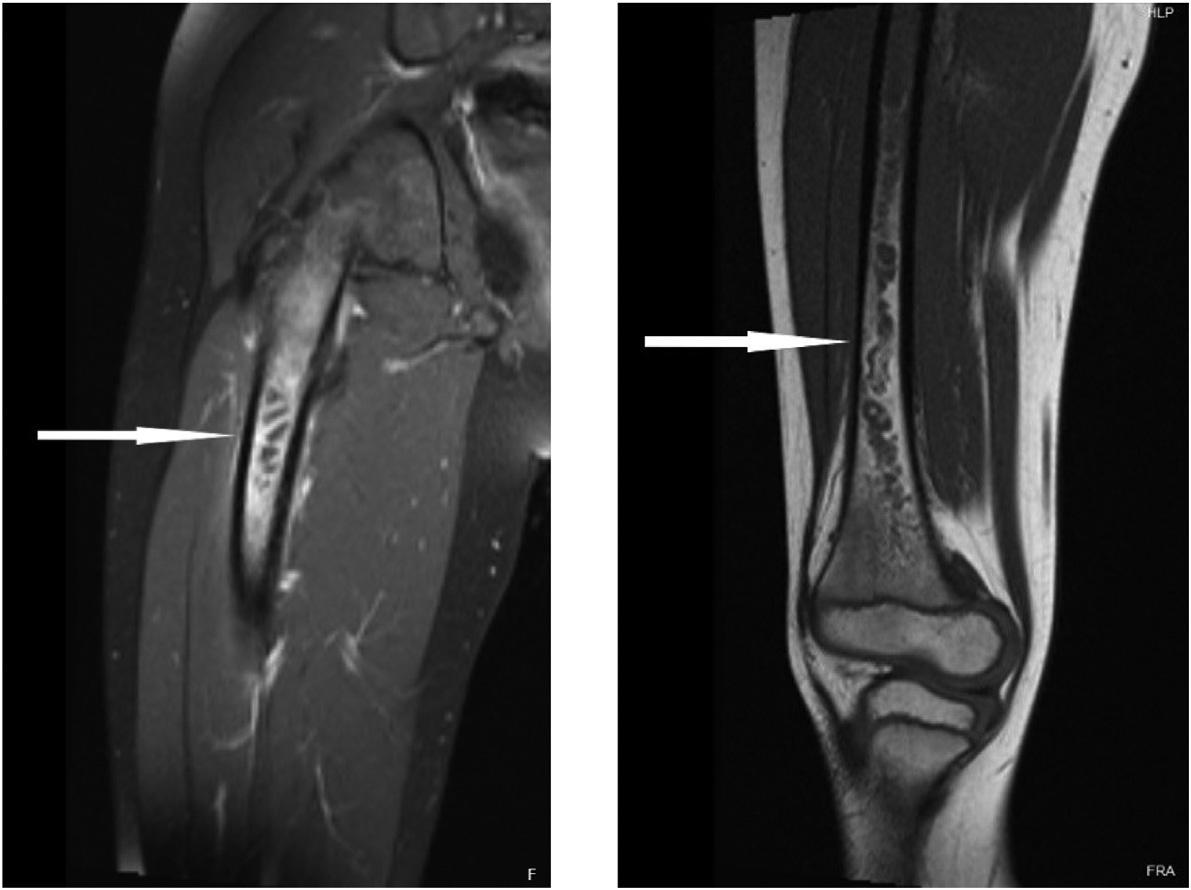

Phone: 1-800-884-2236

222 A Case Report of Delayed Opioid Toxidrome After Administration of Naloxone Maiya Cowan, Prasanna Kumar, Jenny McManus, Sean Bilodeau, Andrew Beck

226 Testicular Traction Technique with Intact Cremasteric Reflex, a Novel Approach for Manual Detorsion: Case Report